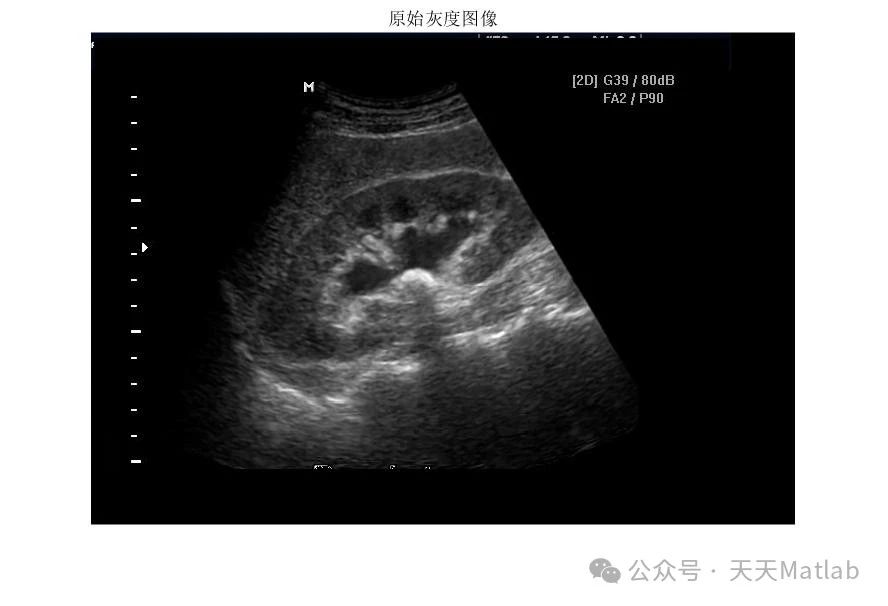

⛳️ 运行结果